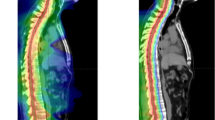

RN is a complication of high dose radiation (used in SRS), which results in the permanent death of irradiated brain tissue. Aside from dose, RN has also been significantly correlated with larger target volumes by several studies [43,44,45]. Resection cavities often remodel unpredictably during the time intervals between surgery, SRS planning, and SRS administration, making it challenging to derive an accurate clinical target volume (CTV) and leaving much variability in clinician practice [46,47,48]. Current consensus contouring guidelines for a clinical target volume include contouring the entire surgical tract (regardless of tumor location), extending the CTV 5–10 mm along the dura overlying the bone flap, and adding 5 mm margin into the adjacent sinus when preoperative venous sinus contact was present [48]. Such a large volume of irradiation leaves parenchymal tissue easily vulnerable to radiotoxicity. The use of hypofractionated post-op SRS (HSRT) appears to be one strategy used recently to reduce the rates of RN for large surgical cavities. nSRS may reduce morbidity associated with RN because the target volume is easily interpretable in scans and therefore, contoured without much interpretation, leaving less tissue irradiated. Furthermore, during surgery, any irradiated rim of healthy tissue is usually removed, resulting in less injured tissue and lower cytokine concentrations required to catalyze RN [14, 19, 33, 49]. Figure 2 shows a treatment planned target volume contour for a patient treated with nSRS and Fig. 3 overlays a mock planned target volume contour (with an additional 1 mm. margin) over the post-operative cavity; these figures illustrate the advantages of nSRS in planning and treatment.

Left temporal post-operative cavity (blue) with an added 1 mm. margin (pink) and mock Gamma Knife plan (yellow; 27 Gy prescription dose, 3 fractions) based on the T1 post contrast MRI images in the coronal a, transverse b, and sagittal c views. This patient was treated with neo-adjuvant SRS prior to surgical resection and is the same patient in Fig. 2